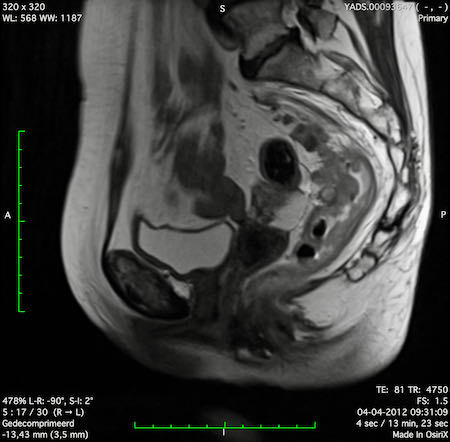

Hình ảnh

Các hình ảnh được cung cấp cho thấy ung thư biểu mô tế bào nhẫn với tình trạng dày lan tỏa thành trực tràng, hình ảnh bia bắn điển hình, và sự xâm lấn mỡ mạc treo trực tràng.